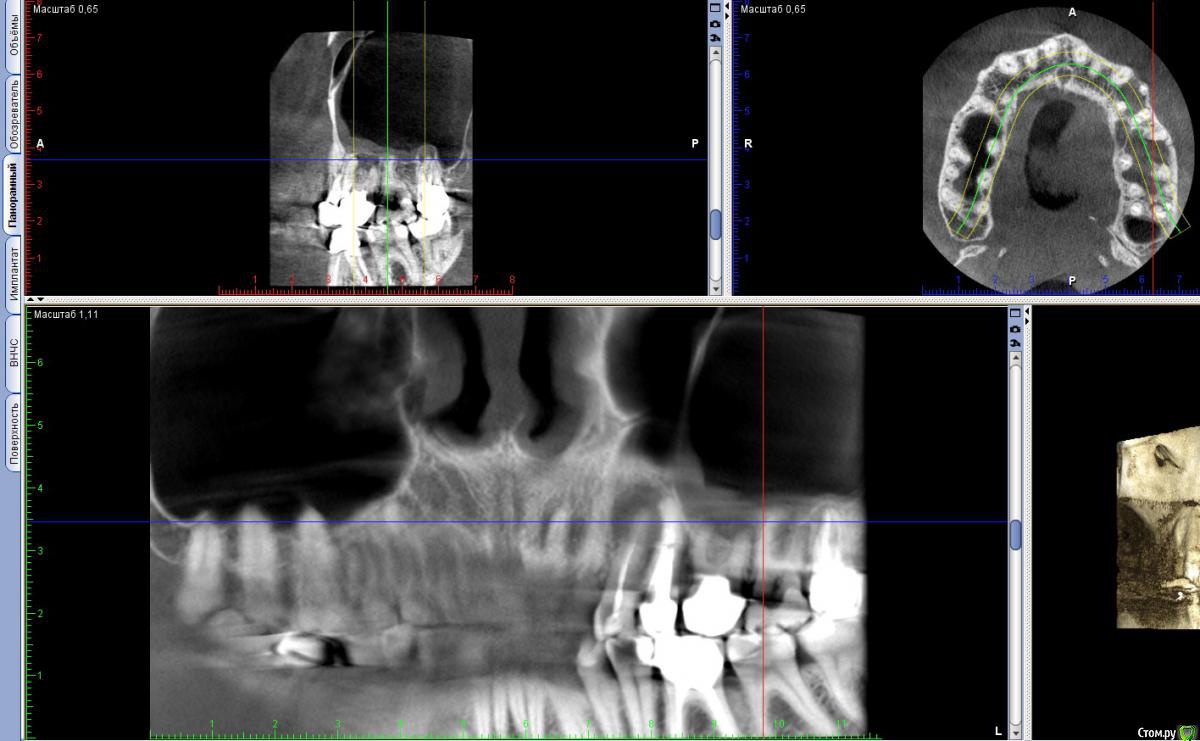

vitavita Опубликовано 4 февраля, 2015 Поделиться Опубликовано 4 февраля, 2015 Начну историю о 6 зубе с самого начала. Когда то давно - лет 30 назад , в советское время мне его кто то лечил , уже не помню кто и как, школьником был. Видимо были удалены нервы. Он меня не беспокоил практически никогда. На обычных ортопанорамных снимках ничего не видно было. 11 лет назад , перед тем как ставить на него коронку , мой доктор пытался пройти каналы, удалось только у принебноого пройти а у 2-х внешних не удалось . Долго пытался , сверла грелись и изнашивались. Сказал что материал там как стекло. Что если когда нибудь заболит то надо будет операцию делать сбоку для резекции корней. Шло время - зуб не болел , я на него нормально жевал и жую до сих пор. Вспоминаю только как то года 3 назад очень жесткое что то попалось и поболел пару дней и прошел. Не придал значения. И вот в ноябре 2014 у меня вдруг обнаружилась киста но на 4-м верхнем левом зубе - нарвало после небольшого ударо по нему сбоку. Хотя ничего не болело. Пошел естественно к врачу . На обычном ортопанорамном снимке толком не видно было. Поэтому отправил доктор меня на томограмму по поводу 4-го зуба и заодно и 6-го , т.к. помним что каналы там не были пройдены. И вот 21 ноября сдел томограмму (если интересно https://yadi.sk/d/Th2NbfMSeULRo). И на ней увидили большую кисту за 4 зубом и кисту у 6-го. Доктор предложил мне удалить 4-й , сделать резекцию 6-го с возможным синус-лифтингом и небольшую резекцию 5-го. И все это одновременно. Напугал возможным гайморитом с очень тяжелыми последствиями. Расстроившись я пошел к другому знакомому хирургу в один из стоматологических институтов. Он предложил сразу сделать резекцию 4-го зуба . Она была удачно проведена открытым способом. 2 месяца походил с йодоформной турундой (менял каждые 10 дней) . Все практически заросло. Теперь спустя 2 месяца встал вопрос о 6 зубе- как с ним быть. Посмотрев томограмму , посоветовашись с другим врачем сказал что все таки резекцию здесь делать нецелесообразно , т.к резать придется 2 корня под корешок , от зуба мало что останется и он долго не простоит. Не жилец. Надо удалять и потом как то протезировать. Послал к терапевту - может можно пройти . Терпавт сказал что для этого надо снимать коронку , но зуб то не болит. Ситуация дурацкая. Отправили к ортопеду , тот сказал что смысла снимать коронку нет , т.к. скорее всего лучше не сделают , а мучаться мне много и никакого результата. Зуб не качается , стоит твордо. И т.к через полгода мне повторно надо будет делать томограмму из-за 4 зуба , то посмотреть динамику развития и кисты и от этого делать выводы. На этом вроде остановились. Теперь у меня 2 выхода :1. или подождать полгода и потом скорее всего удалять2. идти к другому доктору и попытаться сделать резекцию 6-гоСтоит ли бороться за зуб , который к тому же не болит ? Ссылка на комментарий